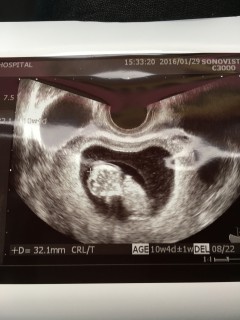

10w2d34.2㎜ 1週間前で、1㎝も成長してくれてました! 寝返りをうつ様なしぐさがと~ってもかわいい。4D画像は手足がくっきりと写し出されていていないいないばぁをしてるようでした。 こんなに小さなからだの力強く動く心臓の音、感動します、すくすく大きくなってね♪

34.2mmで順調に大きくなってくれています☆エコーでは手を動かして指まで吸っていました!!愛おしいです!!早く会いたい(;_;)笑